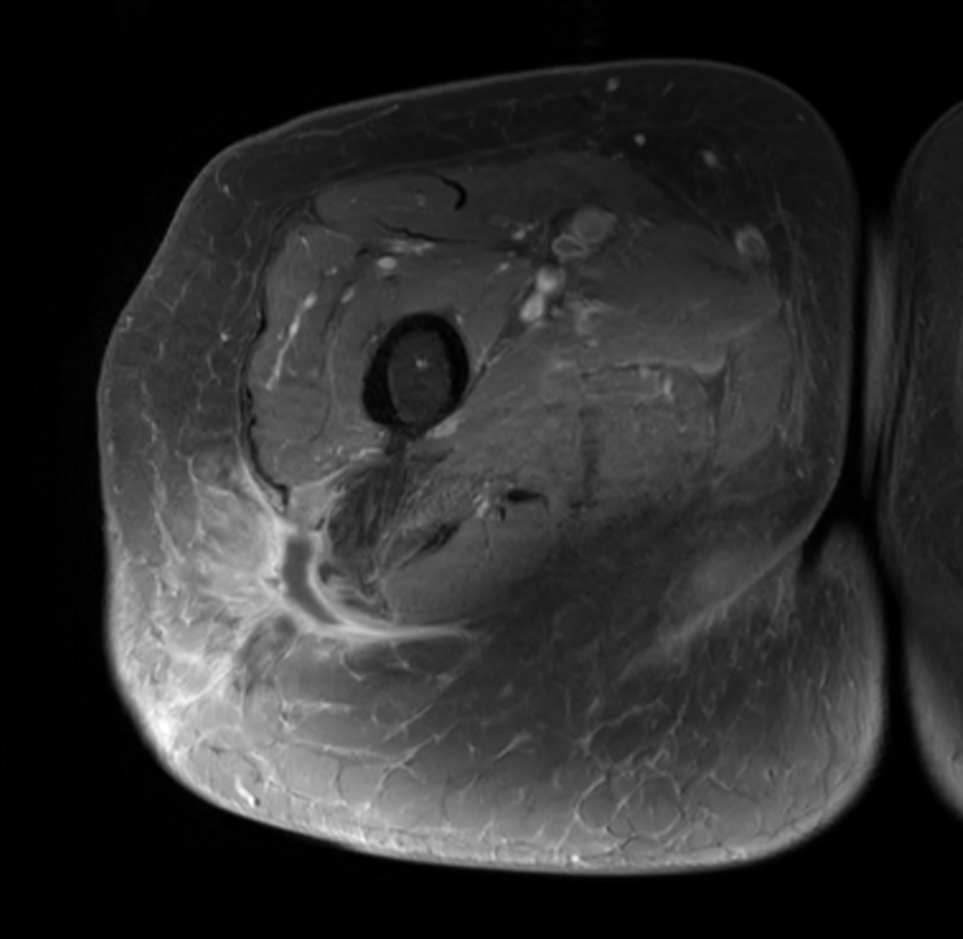

Axial T2w mDIXON XD TSE (Water only)

Axial T2w mDIXON XD TSE (In Phase)